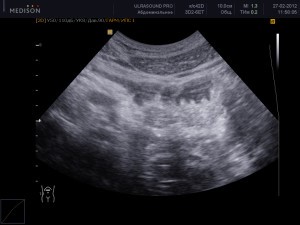

Как проводится УЗИ желудка? Для этой процедуры используется специальный аппарат, который с помощью датчика перемещается по области живота. Ультразвук позволяет визуализировать различные органы брюшной полости на экране. Это исследование помогает выявить некоторые нарушения в работе органов желудочно-кишечного тракта. Однако стоит отметить, что УЗИ не столь информативно, как гастроскопия, поскольку не предоставляет возможности для проведения биопсии.

Что покажет УЗИ в норме

При проведении ультразвукового исследования желудка можно наблюдать следующие нормальные показатели:

- В срезе орган выглядит как овальное образование с кольцевой формой, обладающее эхонегативным ободком и эхопозитивным центром.

- Стенки желудка в проксимальных отделах имеют толщину около 5 мм, в то время как в пилорической зоне – около 7 мм.

- Стенка желудка состоит из 5 слоев, которые различаются по степени эхогенности.

- Серозная оболочка, расположенная снаружи желудка, обладает гиперэхогенными свойствами.

- Мышечная оболочка имеет гипоэхогенные характеристики и толщину примерно 2,5 мм.

- Подслизистая оболочка, обладающая средней эхогенностью, достигает толщины около 3 мм.

- Слизистая пластинка, состоящая из мышечных волокон, обычно низко гипоэхогенна и не превышает 1 мм в толщину.

- Слизистая оболочка имеет толщину около 1,5 мм и характеризуется гиперэхогенностью.

- Выпитая пациентом жидкость покидает желудок примерно за 20 минут, а первичный вывод жидкости в норме составляет около 180 секунд.

- Для оценки перистальтики желудка пациента обычно просят лечь на правый бок.

- Для исключения наличия опухолей необходимо тщательно дифференцировать все слои стенки желудка.

- Важно не только измерять толщину стенок желудка, но и оценивать их равномерность.

При ультразвуковом исследовании желудочно-кишечного тракта также анализируется состояние окружающих тканей: лимфатических узлов и сосудов, а также состояние печени и поджелудочной железы.